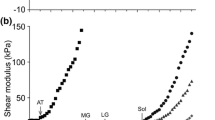

The passive curves for the full stretch ROM at both stretch velocities for both groups are depicted in Fig. 1a and b, respectively. The curvilinear shape was similar for both groups, but the curves for the older women were smaller, steeper and truncated because the maximal passive DF angle was shifted to the left and the maximal passive torque was of lesser magnitude at both velocities. The curves for the fast stretch for both groups showed greater passive resistance compared to the curves for the slow stretch.

Passive stretch curves for the slow 5° s−1 and the fast 120° s−1 stretches for: a the younger women (n = 15), and b the older women (n = 15). Both groups showed increased average passive torque in response to the fast stretch compared to the slow stretch (P<0.001). Note Standard deviation error bars were deleted for clarity

The maximal passive DF angle for the older women (mean 6.8°, SD 4.3°) was less than the maximal passive DF angle for the younger women (mean 24.1°, SD 7.0°) (F=66.69, P<0.001). The mean (± SD) for the maximal passive DF torque, average passive torque, full stretch ROM passive elastic stiffness and total absorbed passive elastic energy for both stretch velocities for both groups are reported in Table 1. The repeated measures ANOVA analyses indicated that all measurements increased for the fast stretch for both groups (P<0.001, Table 1). The fast stretch maximal passive DF torque increased 18% for the younger women and 18.6% for the older women, which were not significantly different. The older women, however, had a significantly greater percent increase (30%) than the younger women (17.5%) for the average passive torque for the fast stretch full ROM (P=0.029) (Fig. 2). The maximal passive DF torque and the average passive DF torque were less for the older women compared to the younger women at both stretch velocities (P<0.001).

The average passive torque through the full stretch ROM for the fast stretch compared to the slow stretch. This was greater for both groups for the fast stretch (**P<0.001), and although less for the older women (*P<0.001), the percent increase was significantly greater for the older women (30%) than for the younger women (17.5%) (P=0.029). Error bars are ±1 SD

The passive elastic stiffness for the older women was greater at both stretch velocities (P<0.001), but the percent increases in the passive elastic stiffness for the fast stretch for the older women (14.3%) and the younger women (17.5%) did not differ statistically. Figure 3 provides a visual comparison of the passive curves for the older and younger women for the slow stretch to illustrate the differences in the passive elastic stiffness (slope) between the two groups. The absorbed passive elastic energy was less for the older women compared to the younger women at both stretch velocities (P<0.001), and both increased for the fast stretch (P< 0.001). The percent increase for the fast stretch, however, was significantly greater for the older women (26%) compared to the younger women (13%) (P=0.005) (Fig. 4).

The total absorbed passive elastic energy through the full stretch ROM for the fast stretch compared to the slow stretch. This increased for fast stretch compared to the slow stretch for both groups (**P<0.001), and although less for the older women (*P<0.001), the percent increase was significantly greater for the older women (26%) than for the younger women (13%) (P=0.005)